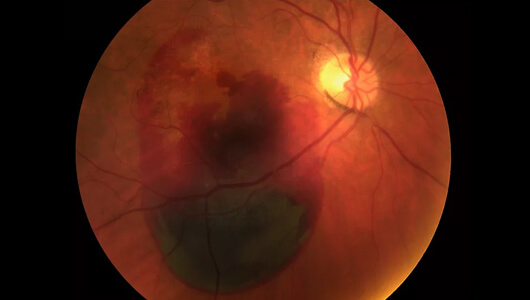

Evo slike mrežnjače još jednog pacijenta - 27-godišnjeg programera koji je došao da ukloni astigmatizam pomoću laserske operacije.

Pomoglo je neko vreme. Pacijent je mogao da živi bez naočara.

Ali, sledeće godine, morao je na još jednu operaciju. Vid mu se pogoršao jer je provodio dosta vremena gledajući u ekran kompjutera.